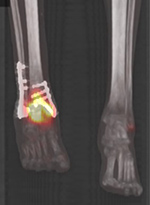

30 year-old man with history of bimalleolar right ankle fracture status post fixation (A, B) presented with fever and sepsis. Technetium 99m MDP bone scan shows increased radiotracer around the right ankle on blood flow (C), blood pool (D) and delayed MIP fused images (E) consistent with osteomyelitis. |

| 30 year-old man with history of bimalleolar right ankle fracture status post fixation. Delayed MIP fused image is consistent with osteomyelitis. |